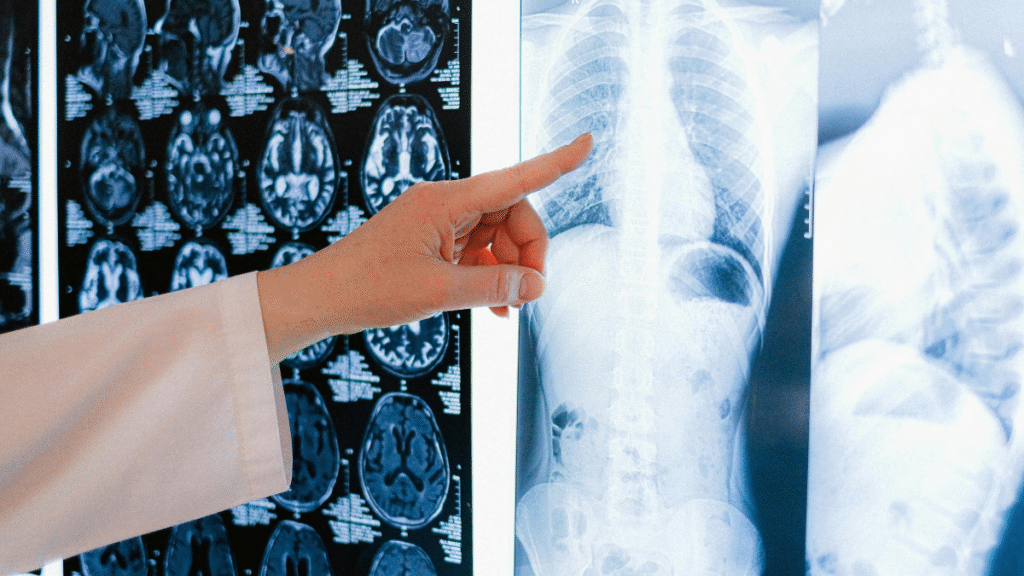

GNH Hospital is widely trusted as the best X-ray hospital in Pune, offering advanced imaging services with precision and care. With modern diagnostic equipment and experienced radiologists, the hospital ensures quick and accurate results for patients.

At GNH Hospital, X-ray services are performed using high-quality machines that minimize radiation exposure while delivering clear imaging. From bone fractures and chest scans to abdominal imaging, patients receive comprehensive diagnostic support. Known as a reliable X-ray hospital in Pune, the hospital prioritizes patient safety, comfort, and timely reporting.

Equipped with the latest machines to provide safe, detailed, and high-quality images.

A team of skilled radiology experts ensures accuracy and efficiency in every report.

All imaging needs including routine and emergency X-rays under one roof.

Transparent pricing with accessible diagnostic care for patients across all age groups.

GNH Hospital has earned recognition as a dependable X-ray hospital in Pune due to its commitment to high standards in diagnostic imaging. Patients can rely on the hospital for accurate results, faster treatment planning, and compassionate care.